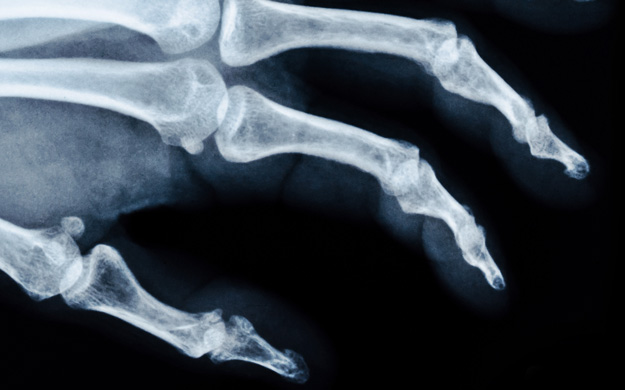

손가락의 관절염은 크게 류마티스성 관절염과 퇴행성 관절염으로 나뉩니다.

두 질환은 근본적으로 발생 원인이 다르며 퇴행성 관절염은 과도한 사용이 원인이 되어 관절이 닳게 되는 퇴행성 질환입니다.

주로 류마티스 관절염은 근위지절을 침범하며 다른 내과적인 증상이 동반할 수 있으며 염증 수치가 올라가고,

퇴행성 관절염은 원위지절을 주로 침범하여 손가락 마디가 두꺼워 지게 됩니다.